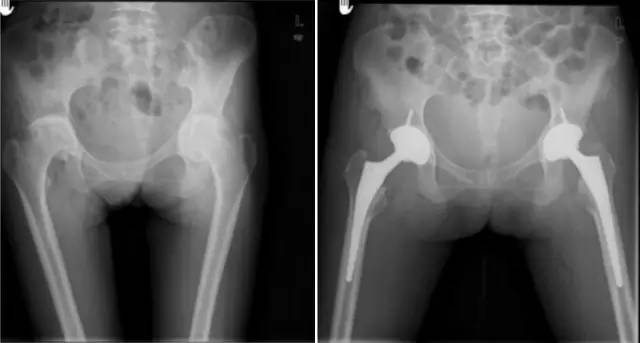

各种晚期骨关节病的关节置换手术治疗是北京清华长庚医院关节外科中心的一大特色,包括股骨头坏死、髋膝骨关节炎、类风湿关节炎、强直性脊柱炎、髋关节发育不良、关节强直、超过80岁的超高龄股骨颈骨折患者的关节置换手术等,我中心在人工关节初次置换及翻修上作了大量工作,置换的难度和手术效果方面已达到国际先进水平,导航下全膝关节置换术:大大提高膝关节置换手术的精确度。

髋关节发育不良

强直性脊柱炎双髋强直